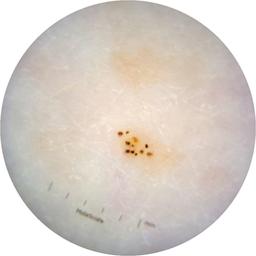

ISIC_6363669

IP_1322385

IL_2591344

acquisition_day 264

age_approx 65

anatom_site_1 Trunk

anatom_site_2 Anterior trunk

anatom_site_general anterior torso

diagnosis_1 Benign

diagnosis_confirm_type single image expert consensus

image_type dermoscopic